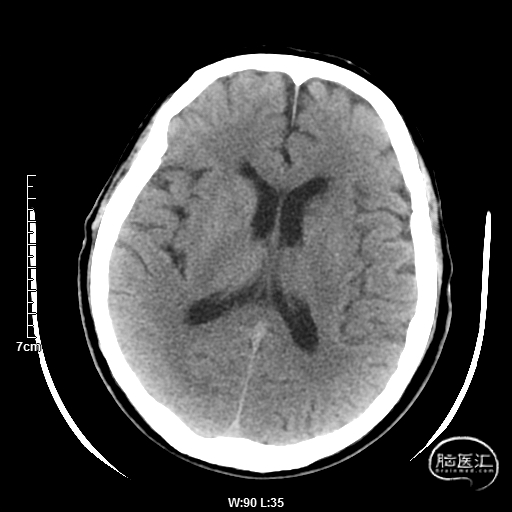

术后9天MRI:

术后半年CTA:Bridge支架形态及贴壁良好,前向血流正常。